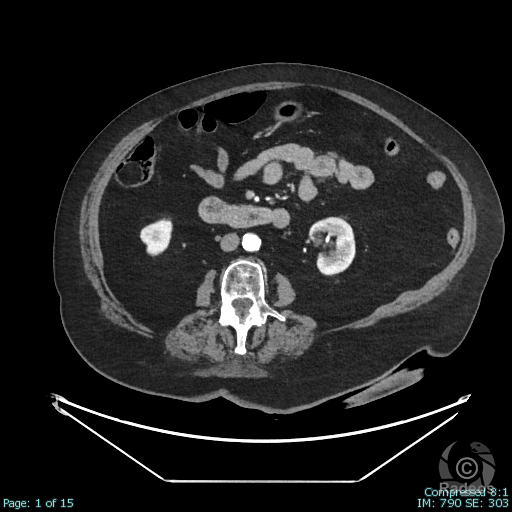

Aspect IRM d'une fibromatose profonde de la paroi abdominale. Découverte fortuite d'un angiome hépatique gauche.

Fibromatose profonde de type desmoïde